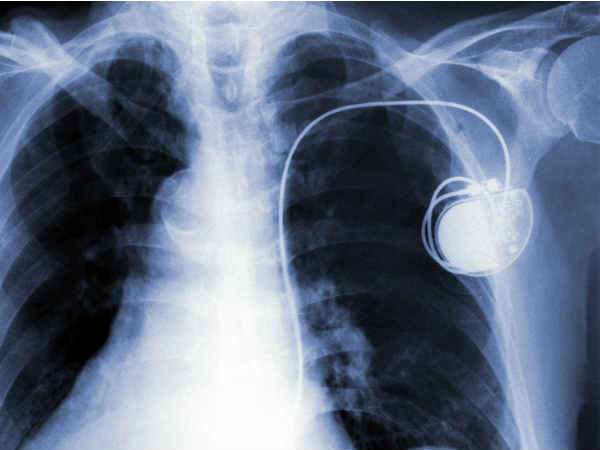

पेसमेकर के बारे में जानिए कुछ जरुरी बातें

पेसमेकर एक छोटी सी डिवाइस होती है जिसका वजन मुश्किल से 25 से 35 ग्राम होता है। इस डिवाइस को उन मरीजों के दिल में फिट किया जाता है जिनका हार्ट रेट कम होता है, यह डिवाइस ह्दय की मांसपेशियों में इलेक्ट्रिक इम्पल्स भेजती है, जिससे आर्टिफिशियल हार्ट बीट बनती है और हार्ट रेट सामान्य आ जाता है।

पेसमेकर को दिल के लेफ्ट या राइट कॉलर बोन में त्वचा के नीचे फिट किया जाता है और नसों से जोड़ा जाता है। एक पेसमेकर लगभग 10 से 12 साल चलता है। इसे लगवाने के बाद व्यक्ति सामान्य जीवन जी सकता है। आइए जानते हैं पेसमेकर के बारे में अन्य खास बातें: